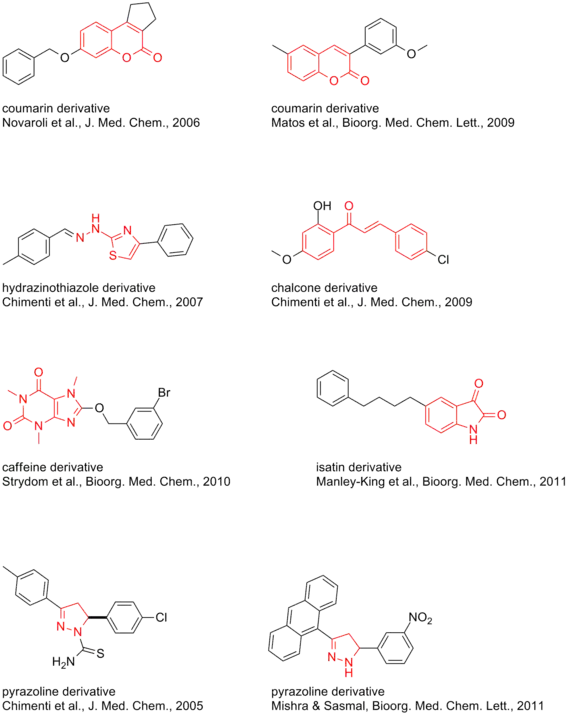

Species-dependent divergences may hamper the extrapolation of inhibitor potencies.[33]

Reversible

Natural

Synthetic

- Safinamide and analogs[38]

- 5H-Indeno[1,2-c]pyridazin-5-ones[33][39][40] (see 3d model)

- Substituted chalcones[41]

- 2-(N-Methyl-N-benzylaminomethyl)-1H-pyrrole[42]

- 1-(4-Arylthiazol-2-yl)-2-(3-methylcyclohexylidene)hydrazine[43]

- 2-Thiazolylhydrazone[44]

- 3,5-Diaryl pyrazole[45]

- Pyrazoline derivatives[46][47]

- Several coumarin derivatives[48] and #C19*[33] (see 3d model)

- Phenylcoumarins, extremely subtype selective[49] and further analogs[50][51][52] (see 3d model)

- Chromone-3-phenylcarboxamides[53]

- Isatins[54]

- Phthalimides[55]

- 8-Benzyloxycaffeines[56][57] and CSC analogs[58]

- (E,E)-8-(4-phenylbutadien-1-yl)caffeines,[59] with A2A antagonistic component

- Indazole- and Indole-5-carboxamides[60]